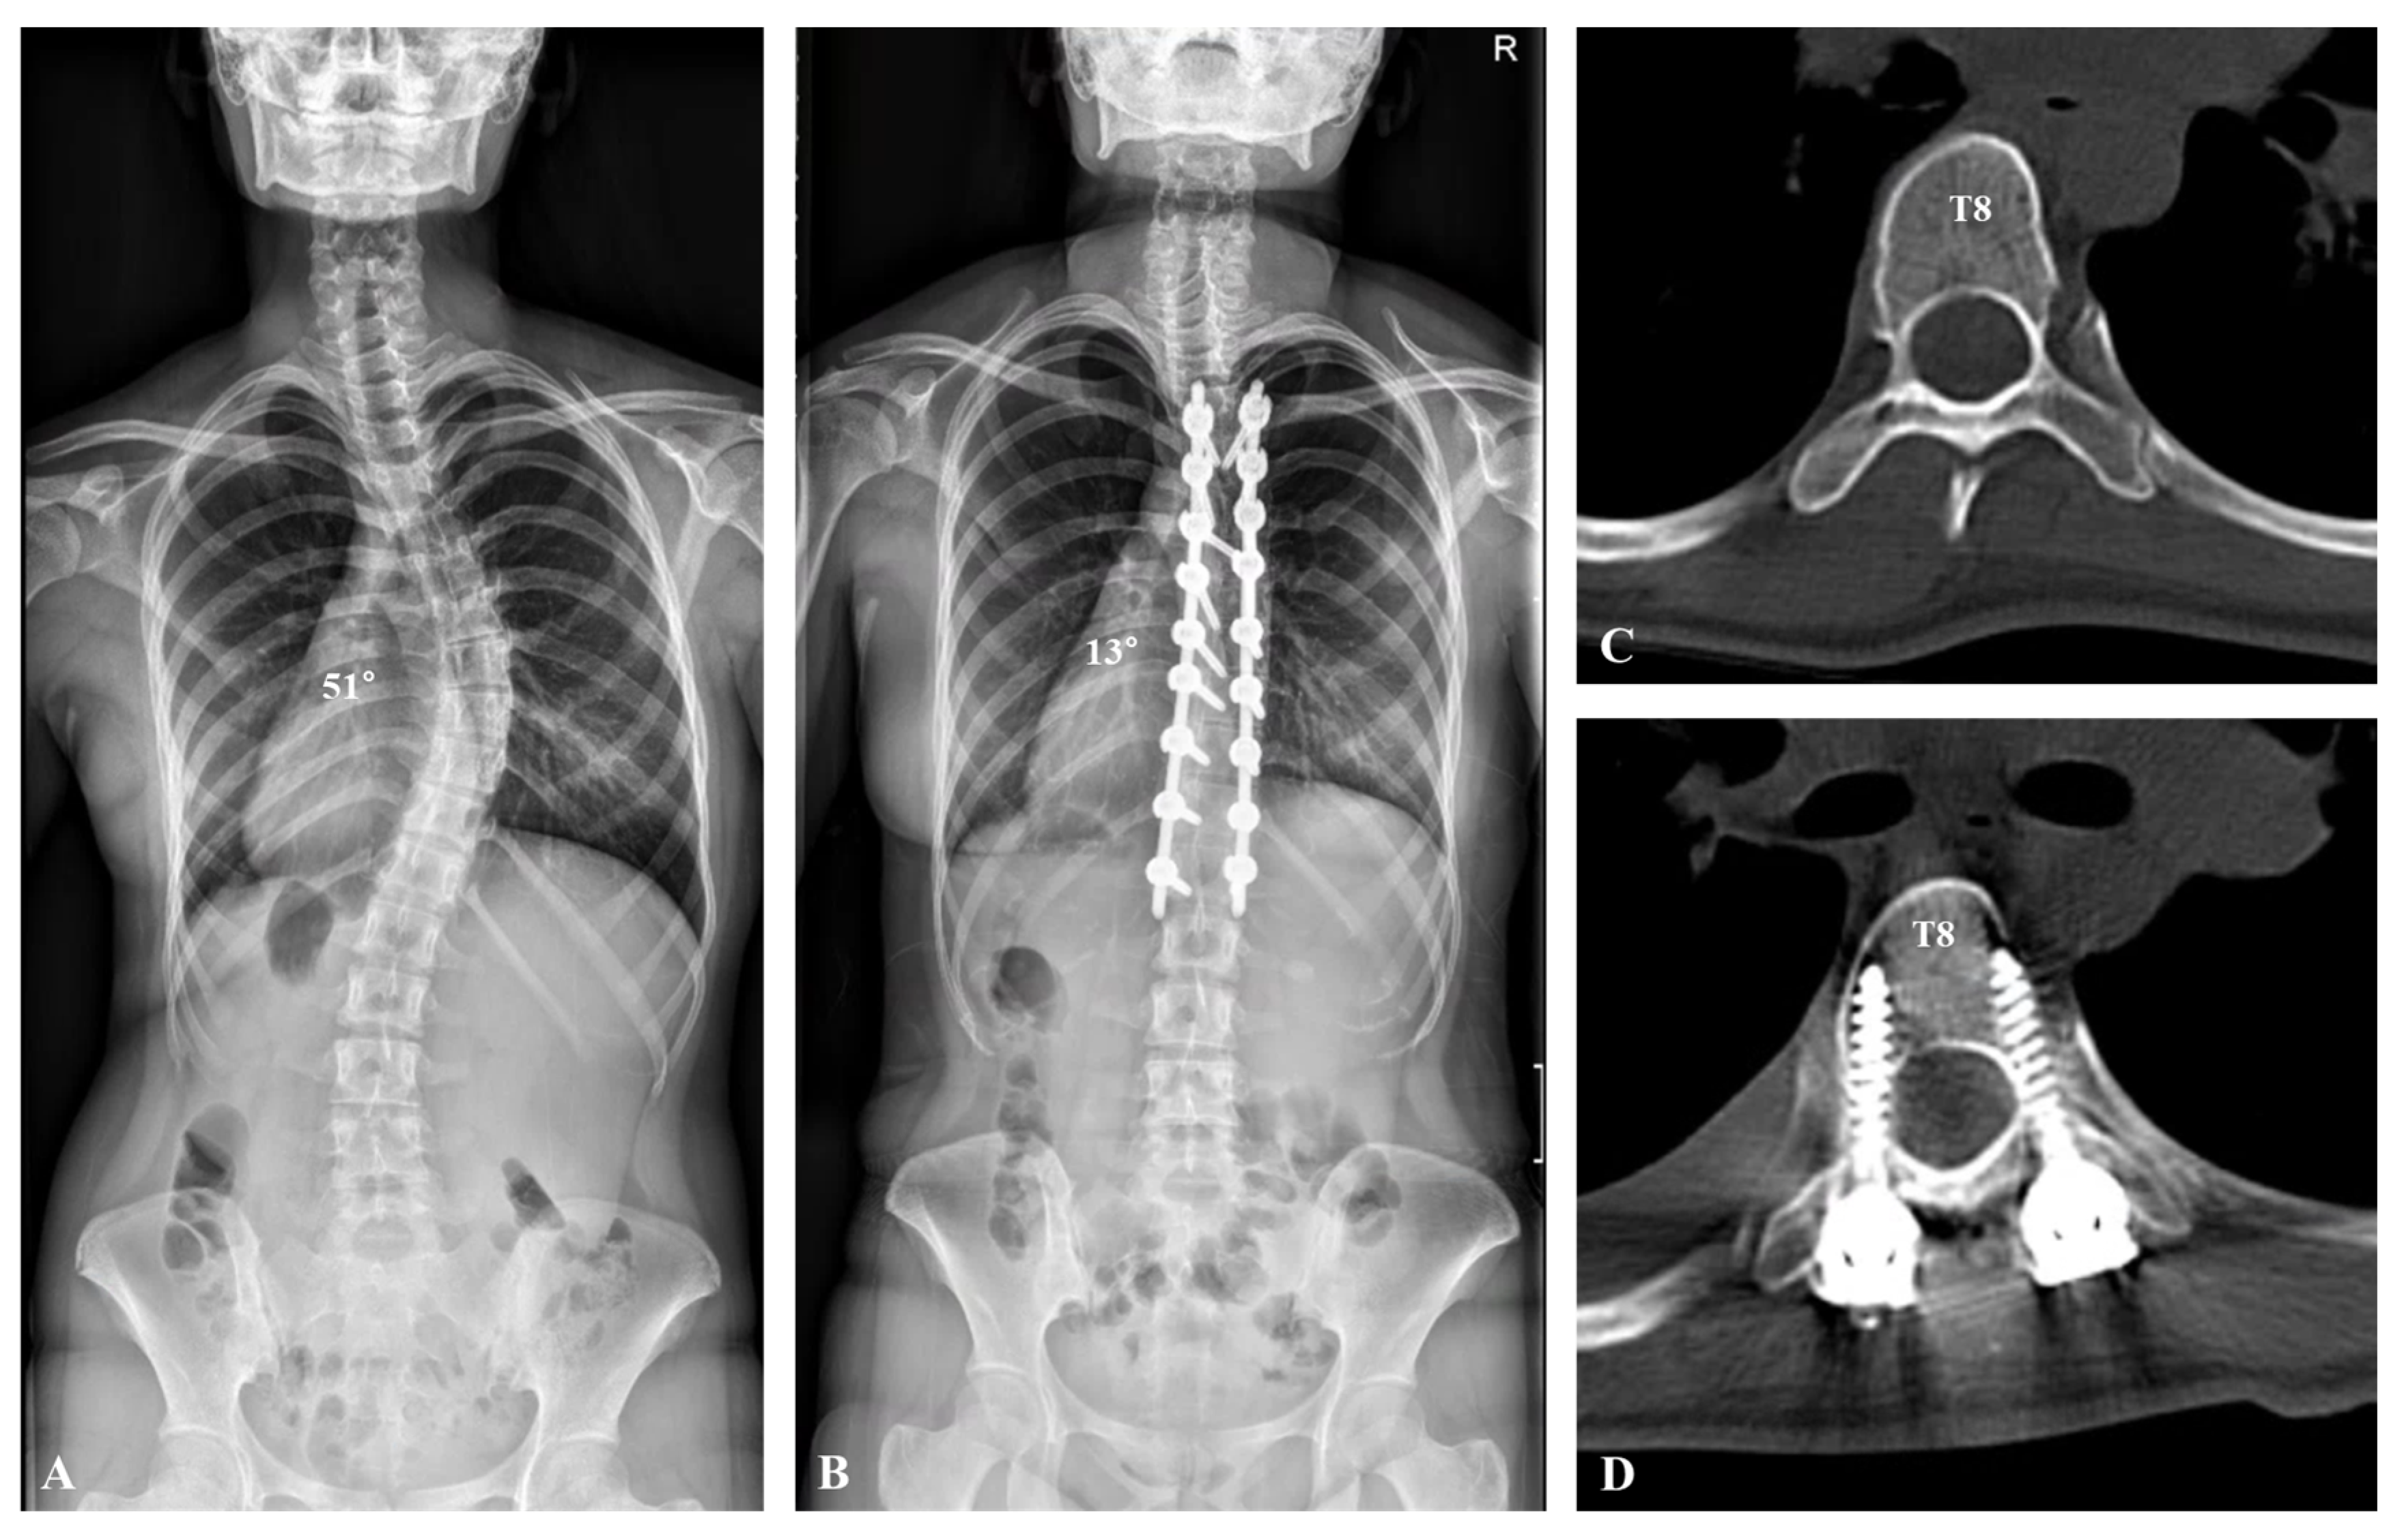

| Postoperative (°) | 17.4 ± 5.4 | 21.0 ± 5.9 | 0.043 |

| Correction rate (%) | 70.2 ± 5.9 | 65.3 ± 8.9 | 0.04 |

| 3-month follow-up (°) | 17.5 ± 5.1 | 21.5 ± 4.8 | 0.046 |